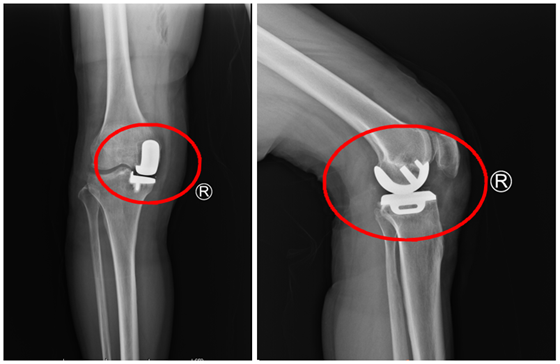

近期,湘雅常德医院骨科连续开展两例膝关节单髁置换手术,解决了患者因膝关节退变而产生的疼痛及功能障碍。与全膝置换术相比,膝关节单髁置换术切口及膝关节内损伤更小,患者术...